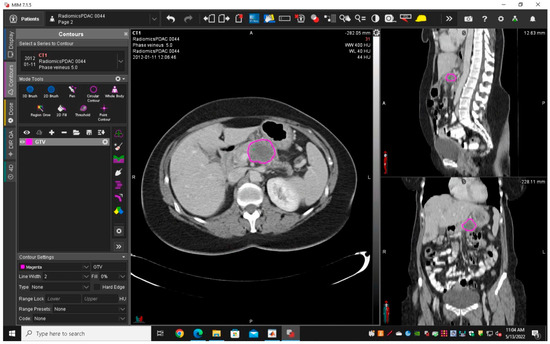

2.3.1. Segmentation and Features Extraction

| GTV | Gross tumour volume |